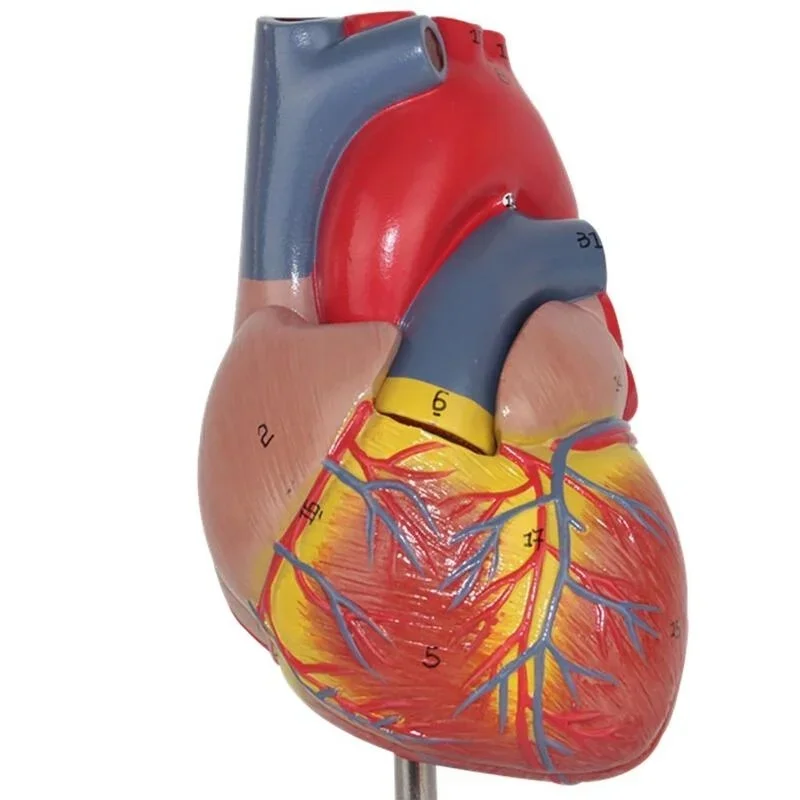

Фотографии и 3D-модели анатомии сердца человека